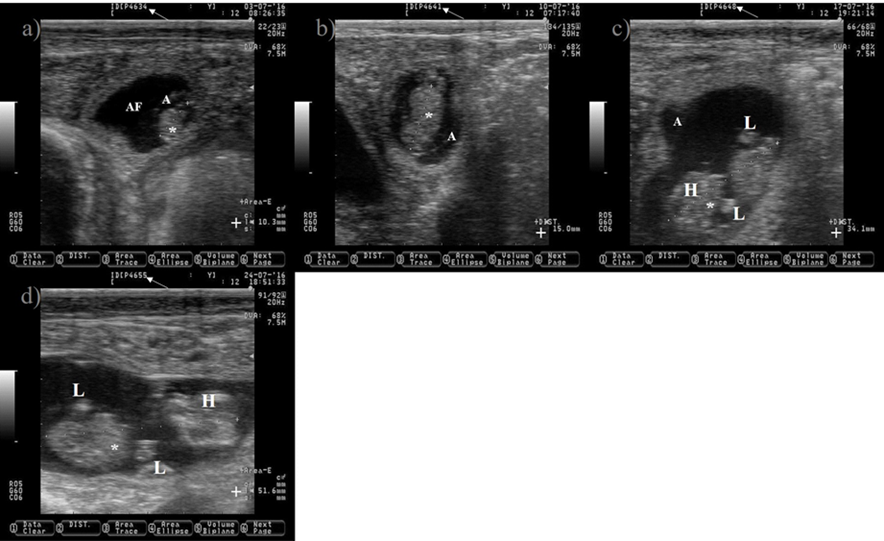

White arrow is pointing at days of gestation. a) 34-d old embryo. b) 41-d old embryo. c) 48-d old embryo. e) 55-d old embryo.

*= embryo; A= amnion; AF= allantoic fluid; += size of the embryo; H= head; L= limbs. Pictures were taken using a 7.5 MHz probe. Pictures correspond to the same embryo.

Figure 8 Pictures depicting embryo development in Holstein dairy cattle from 34 to 55 d of gestation